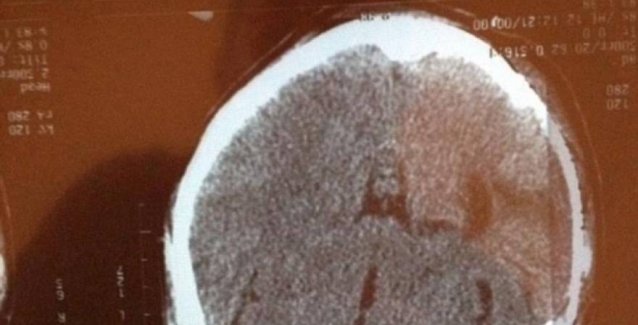

Τη μορφή του Ιησού υποστηρίζει ότι βλέπει σε ακτινογραφία του κρανίου της, μία γυναίκα από το Μεξικό όπου υπέστη εγκεφαλικό επεισόδιο ενώ νοσηλευόταν με σοβαρό πρόβλημα υγείας στους πνεύμονες.

Ο σύζυγός, Ταμάχα Μακ Ντόναλντ είπε ότι έβλεπε μαζί με τη γυναίκα του τις ακτινογραφίες του κρανίου της, όταν παρατήρησαν τη μορφή του Ιησού.

«Είμαστε σίγουροι και οι δύο, ότι είναι το πρόσωπο του Ιησού», δήλωσε ο Μακ Ντόναλντ στην ιστοσελίδα Stuff.co.nz. «Η μορφή του αναπαριστά ένα θαύμα», υποστηρίζει ο ίδιος.

Ωστόσο, οι θεράποντες ιατροί υποστηρίζουν ότι το ζευγάρι υποφέρει από παρειδωλία, δηλαδή την ψευδαίσθηση ότι βλέπουν μια γνώριμη μορφή σε ένα άψυχο αντικείμενο.